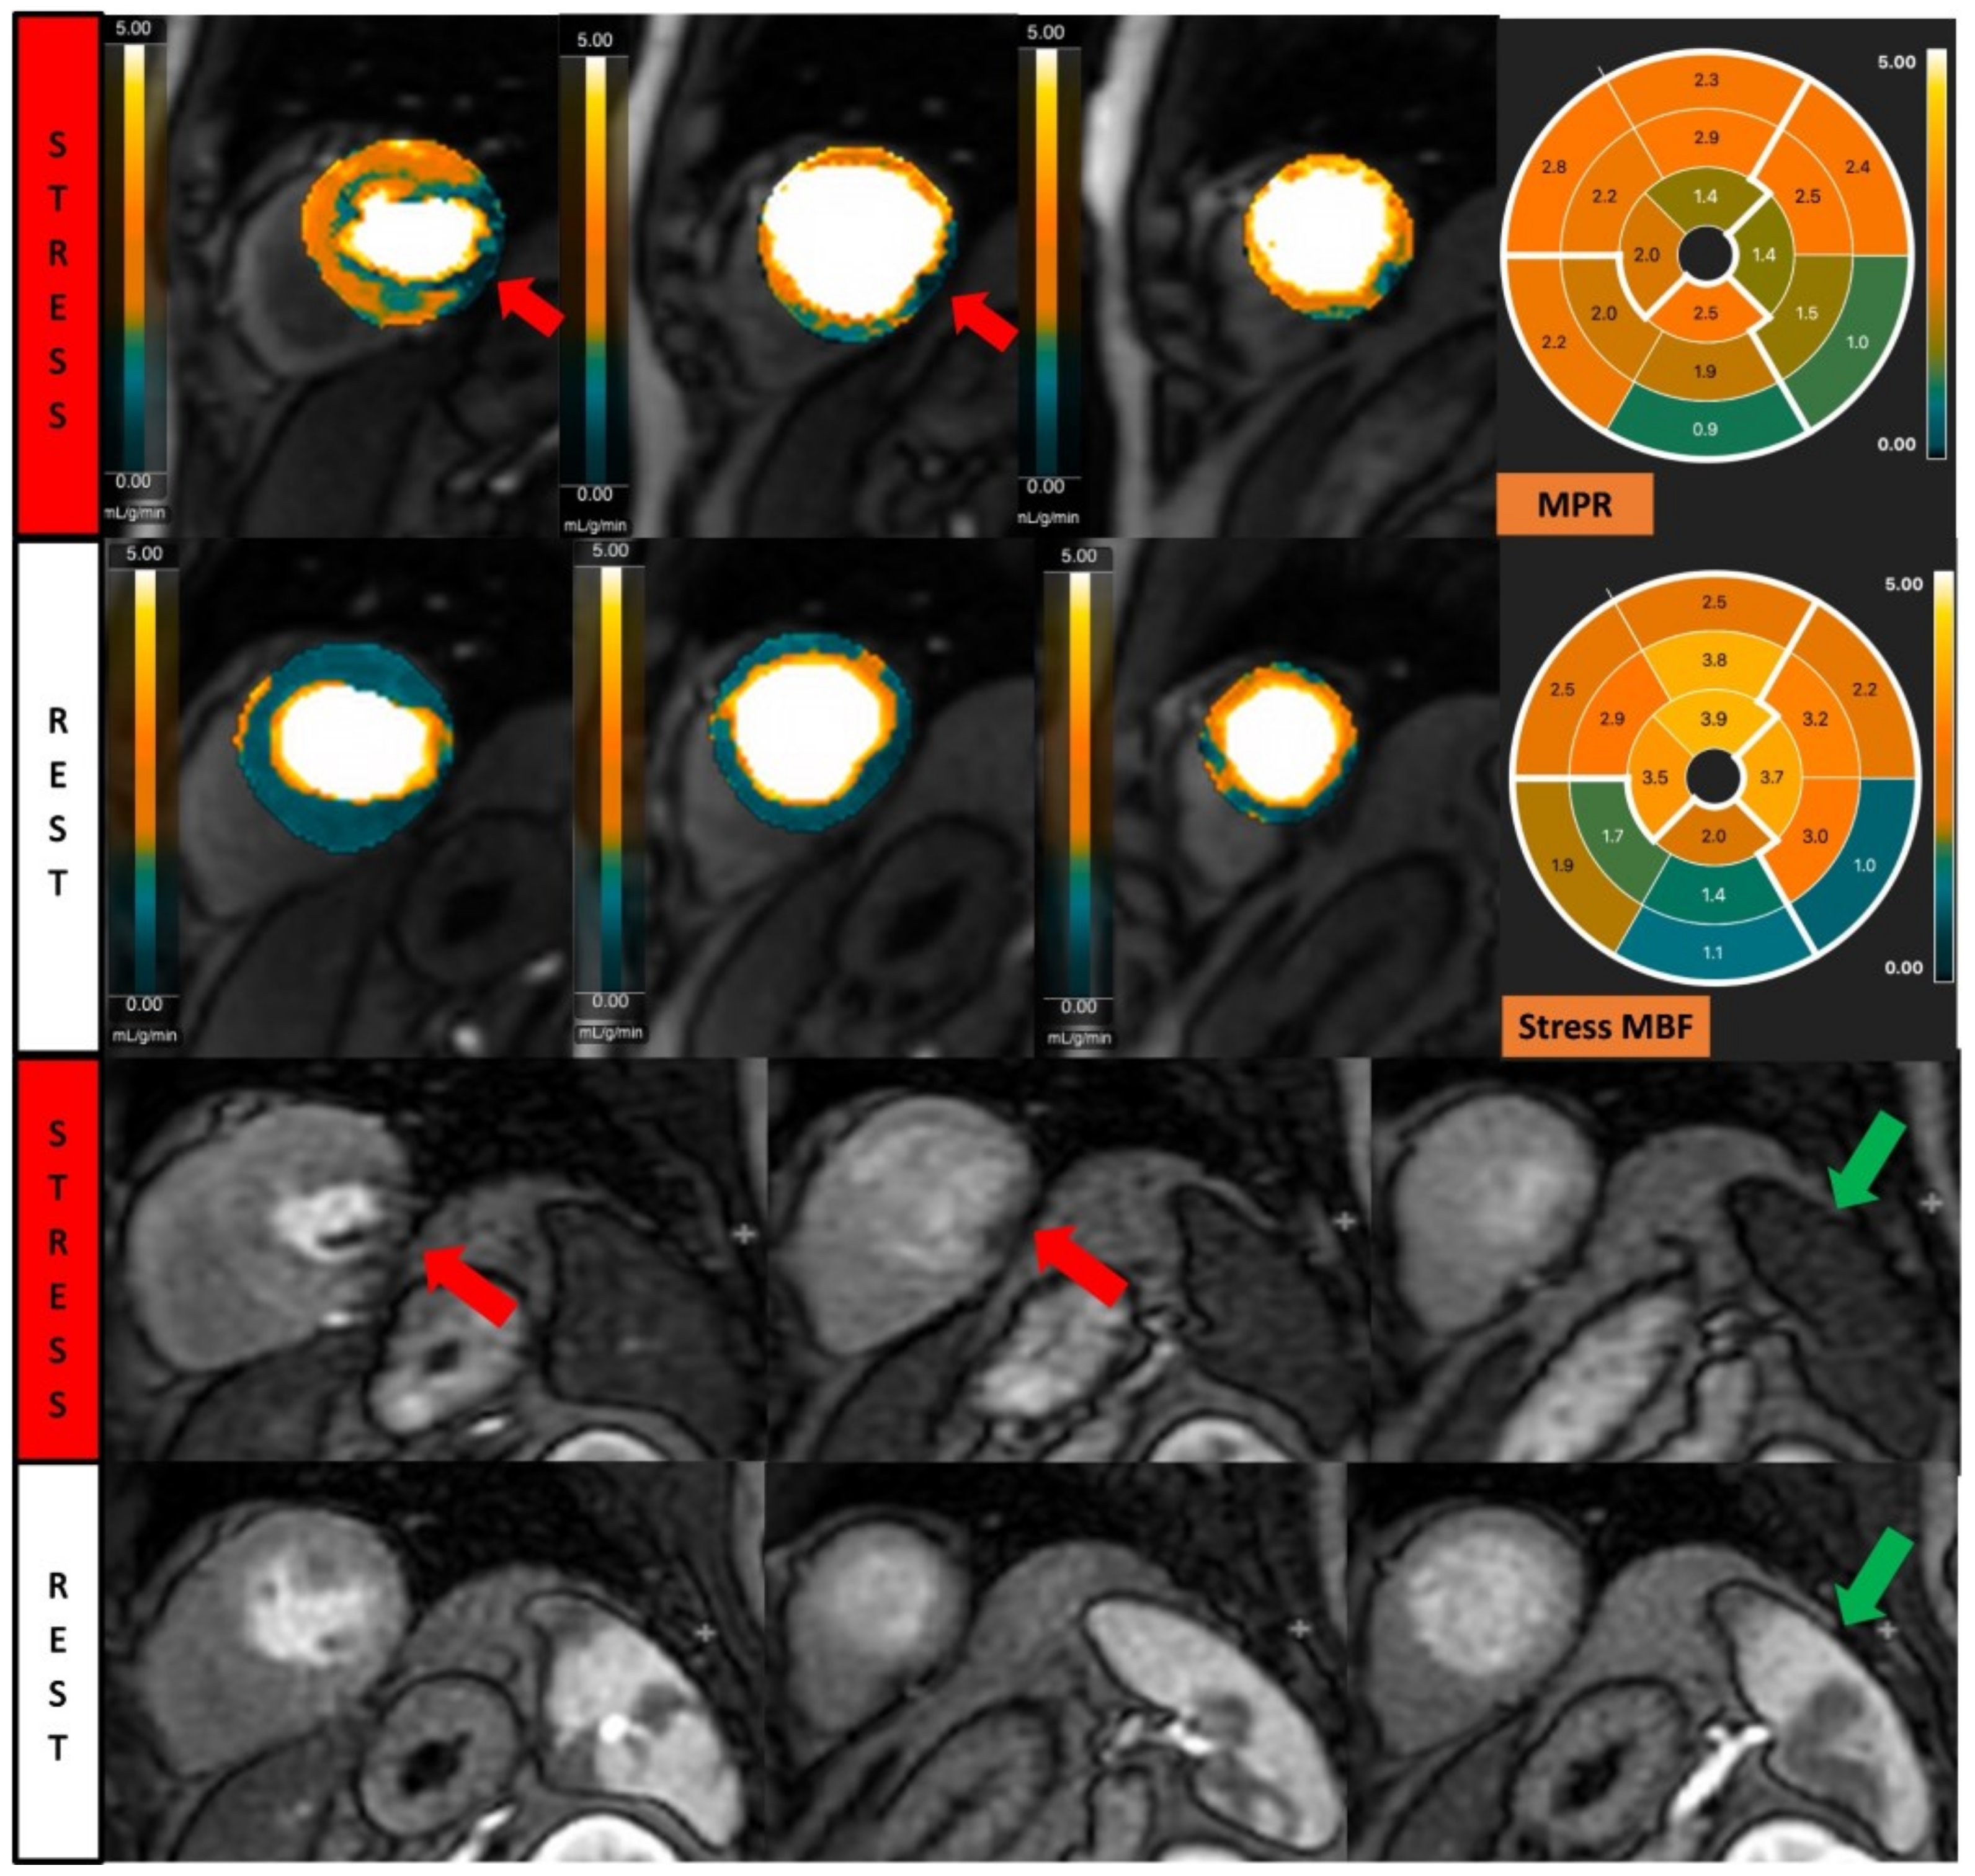

Fully quantitative analysis of myocardial blood flow (MBF) of significant CAD. Male, 55 years old, presenting with chest pain during hiking. CCTA showed chronic total occlusion in left circumflex artery (LCx). Quantitative stress perfusion images (top row of images) and standard stress perfusion images (2nd bottom row) showed hypoperfusion in the lateral wall from base to mid-ventricular slice (red arrow), corresponding with reduced stress MBF in LCx-supplied area. Green arrows highlight the splenic switch-off sign, with the spleen showing reduced perfusion during stress and increased perfusion during rest.

Figure 5.

Contoured perfusion image (left) and signal intensity graph (right). Left panel demonstrates the contouring of right ventricle (yellow circle) and epicardium (green circle) and subendocardium (red circle) of left ventricle. Right panel shows the signal profile of each segment and blood pool.

Figure 7.

Fully quantitative analysis of stress CMR examination showing coronary microvascular dysfunction. Male, 66 years old, asymptomatic with past history of diabetes, hypertension, and hyperlipidemia. CCTA showed non-obstructive CAD, and stress CMR showed a splenic switch-off sign and no visual perfusion defect during stress. However, fully quantitative analysis showed extensive reduced MPR, not correlated to a coronary distribution, which may be caused by CMD.